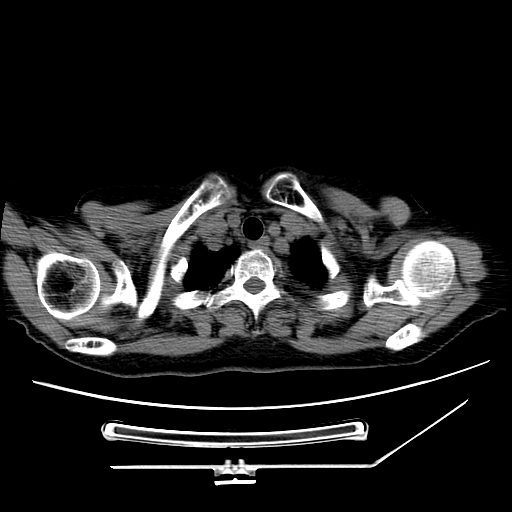

标题: CT25393:病人45岁,咳嗽,吐黄痰带血丝,发热,胸闷月余 [打印本页]

标题: CT25393:病人45岁,咳嗽,吐黄痰带血丝,发热,胸闷月余

1、左肺中央型肺癌并双肺弥漫性转移   2、双肺部感染    3、肺大泡     4、左侧胸腔积液

双侧肺弥漫性病变,可见“空泡征”及“蜂窝征”,考虑肺泡癌可能性大,左侧胸腔积液,考虑胸膜受累可能!

1)不排除肺泡癌可能。2)左侧胸腔积液。